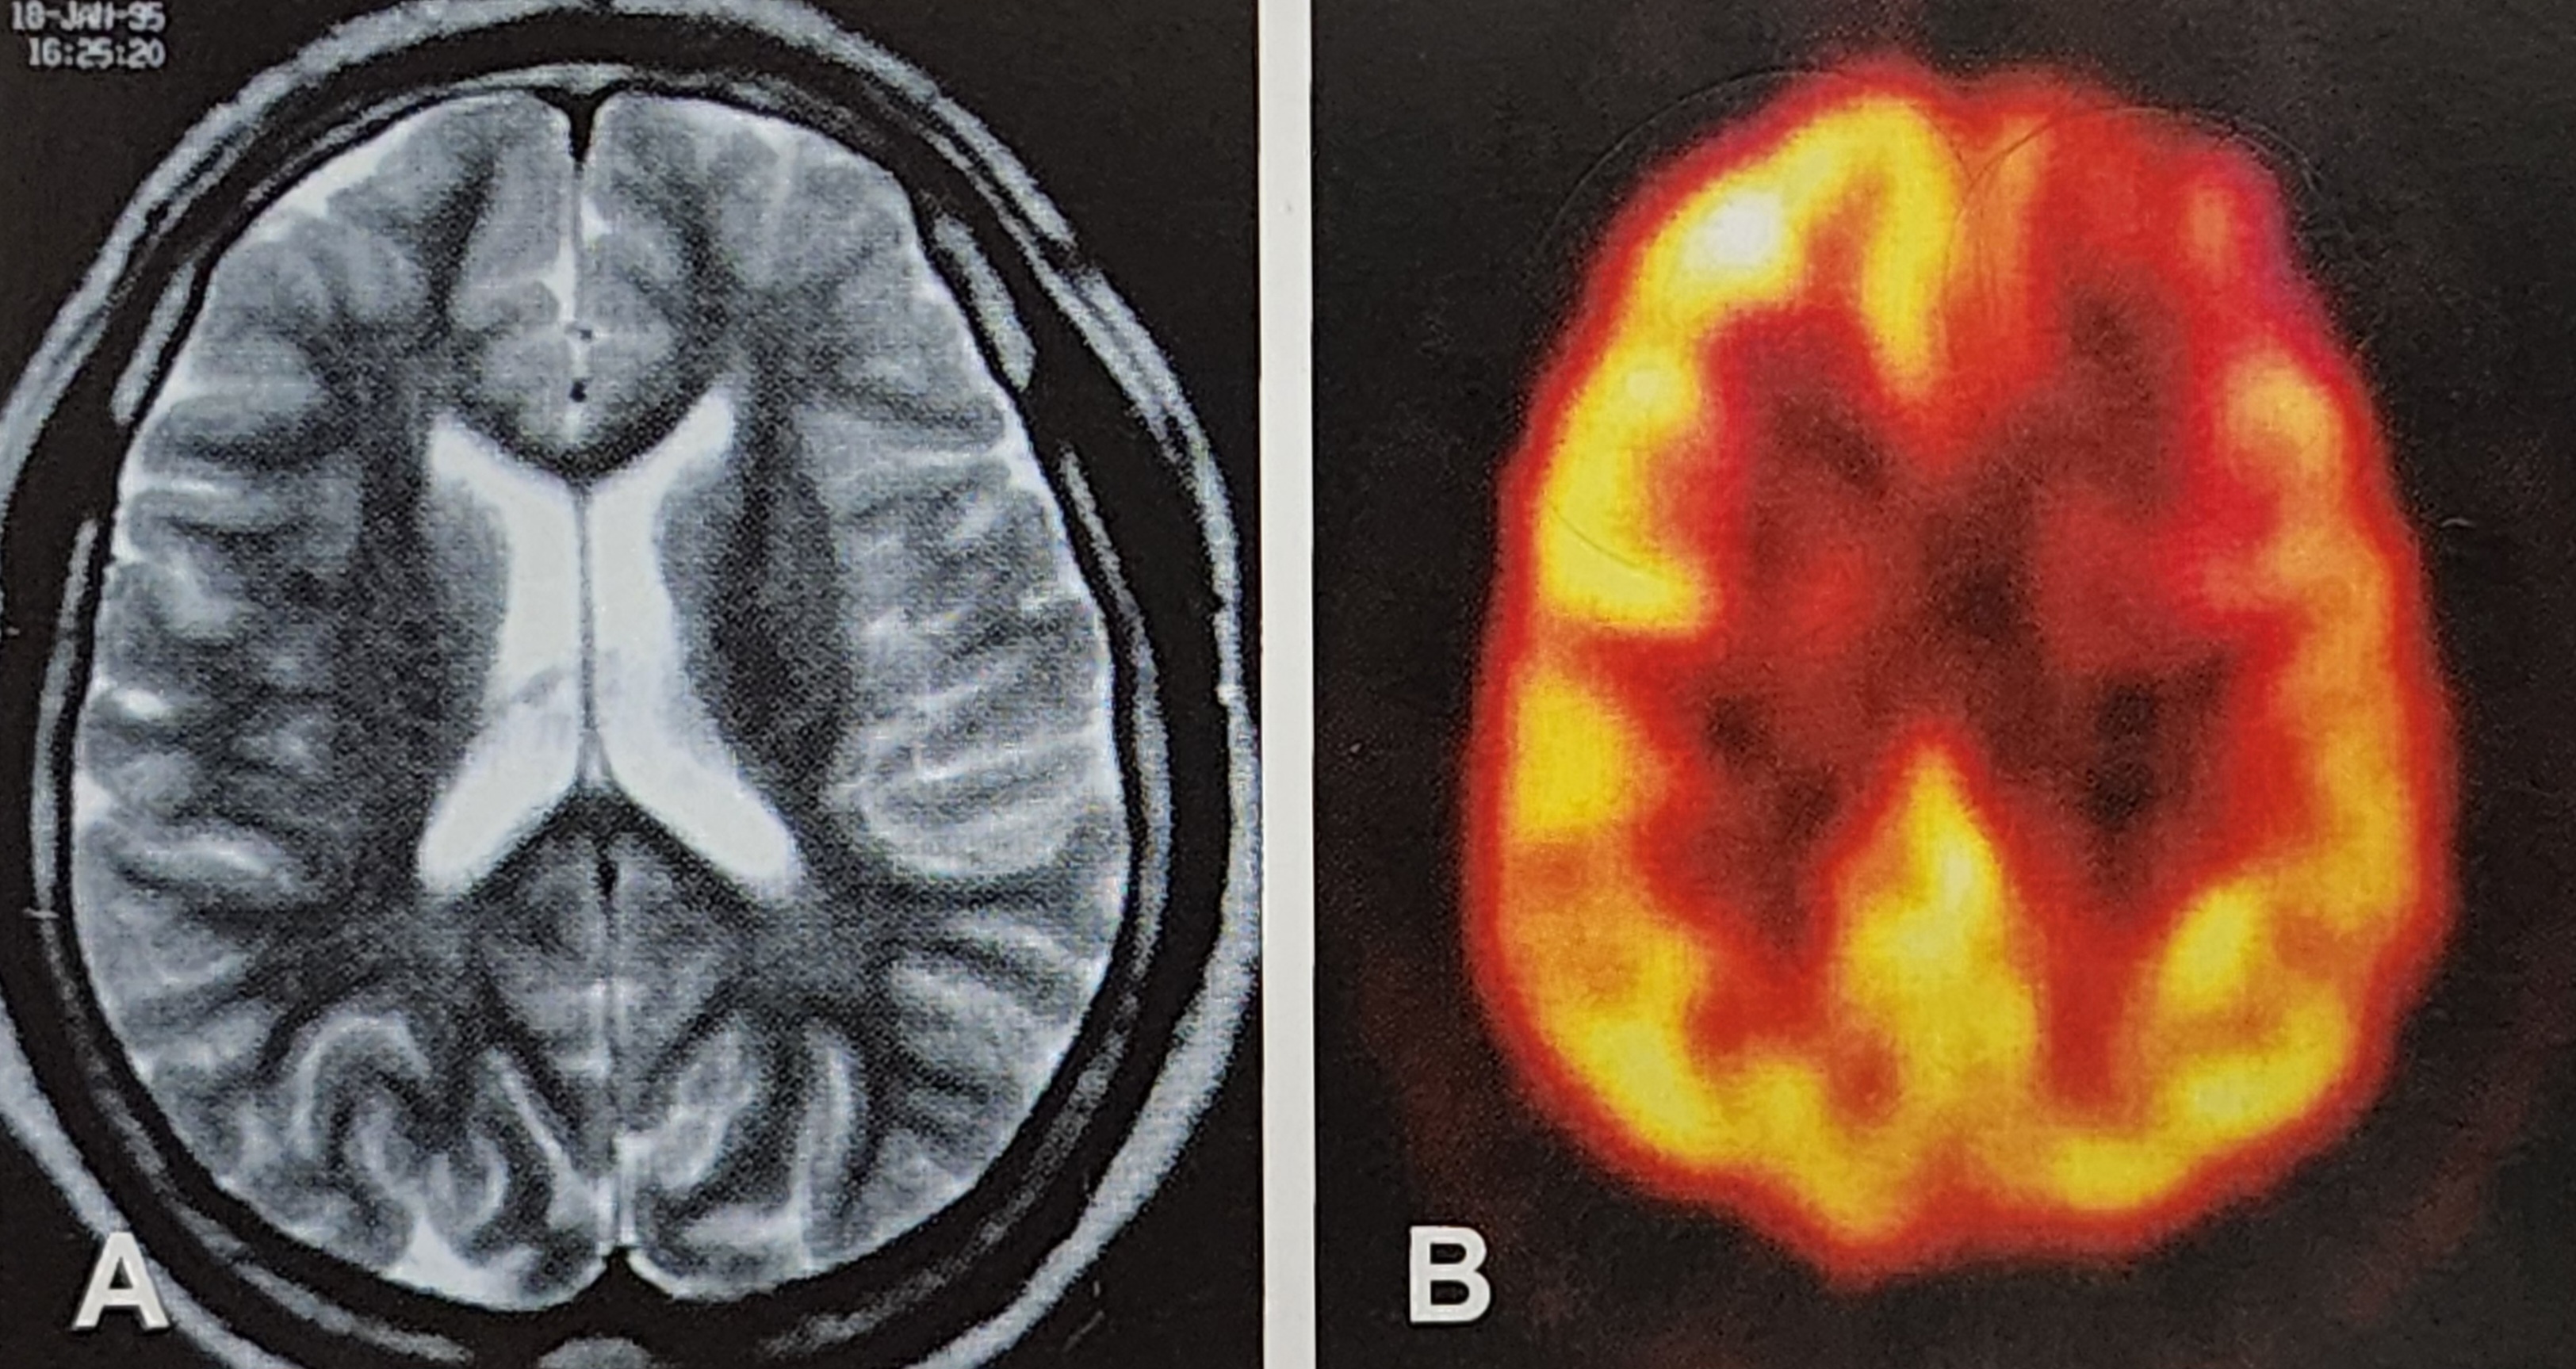

FDG-PET는 방사성 동위원소를 이용하여 뇌의 대사 상태를 분석하는 기술입니다. 이 기술은 특히 포도당 대사가 활발한 영역과 비활성화된 영역을 명확히 보여줄 수 있어 뇌전증, 치매, 뇌종양과 같은 신경 질환을 진단하는 데 널리 사용됩니다.

- 원리: FDG(플루오로데옥시글루코스)는 포도당과 유사한 성질을 가진 방사성 표지 물질로, 뇌세포가 포도당을 사용하는 대사 과정을 시각화합니다.

- 장점: FDG-PET는 특히 MRI나 CT에서 명확히 드러나지 않는 미세한 대사 변화를 포착할 수 있습니다.

FDG-PET 사례

예를 들어, 내측두엽뇌전증(Medial Temporal Lobe Epilepsy)에서는 MRI로 명확히 보이지 않는 해마의 대사 저하를 FDG-PET로 확인할 수 있습니다. 이는 특히 약물 난치성 뇌전증 환자의 수술 성공률을 높이는 데 기여합니다.